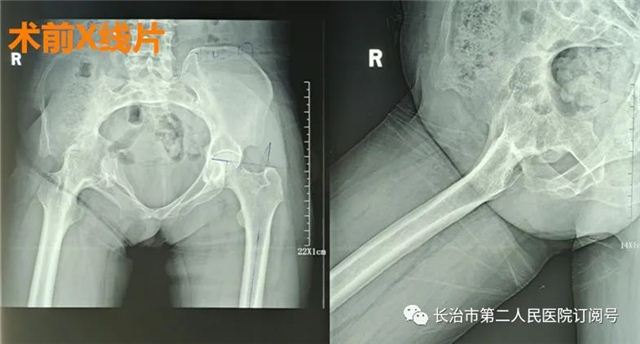

你能快速说出人体的关节名字吗? 相信有不少人 第一反应都会说出膝关节 有多少人知道人体最大的关节 髋关节呢? 髋关节 是人体连接躯干 和下肢的重要关节 人体直立行走时 依靠双侧髋关节支撑 如奔跑、行走、攀登等剧烈运动 需依靠髋关节 带动躯干完成不同动作 所以它也是人体最重要的关节之一 如果髋关节“叛变”了 问题就十分严重了 近日 48岁的张女士就因为“髋痛” 严重影响她的生活质量 究竟是怎么回事呢 据了解 在她15岁那年 右髋无故出现发热肿痛的症状 当地医院考虑 右髋关节感染予以行 右髋关节切开清创术 因引流口持久不愈合伴窦道形成 持续换药4个月后愈合出院 出院时右下肢已严重萎缩 右髋自发融合于屈髋40度 固定畸形 严重跛行步态 就这样 她忍受了33年之久 手术中,医生对于张女士截骨的位置和角度都需要极小心地判断,需要采用二次截骨法截断股骨颈,否则极易误伤髋关节周围的肌肉、神经和骨盆。由于她髋关节强直已有33年,髋周围肌肉长期废用性萎缩,对人工髋关节的保护能力很差,术后如何避免髋关节脱位是关键,需要医生术前严格仔细计划,术中准确把握髋关节假体安装角度;由于化脓性髋关节炎导致的骨性融合髋,原发致病菌是否已完全控制,术后有无可能原潜伏的病原菌死灰复燃导致假体感染发生,对于患者及医护人员提出极高考验。 科室介绍 长治二院关节外科一病区张鹏主任团队以“微创治疗、无痛手术、潇洒行走”的理念,将矫形外科、关节镜微创外科、运动医学的技术理念结合起来治疗各种关节疾病,是国内较早开展膝关节单间室置换术和肩关节置换术的科室之一。 门诊时间安排: 周三上午:李晓东院长 周一上午:张 鹏 周一下午:杨惠强 周二全天:王子江 周三全天:杨惠强 周四全天:张 鹏 周五全天:李向毅 地址:长治二院门诊二楼关节一诊室 联系电话:15635580253(张主任) 科室电话:0355-3126023 欢迎关注“骨关节疾病诊治”,微信号czey-gjwkybq